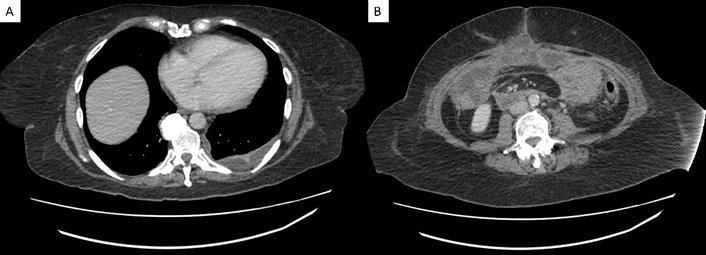

Seven days after the endoscopy, the patient presented to her local emergency department with progressively worsening symptoms. Upon presentation, the patient was tachycardic (heart rate 105 bpm), dehydrated, and exhibited mild lower abdominal tenderness. Laboratory tests revealed ALB 2.9 g/dL, HGB 9.8 g/dL, and a negative Clostridioides difficile PCR. Abdominal and pelvic computed tomography (CT) in the emergency department demonstrated fluid-filled small bowel loops with mild circumferential wall thickening involving the splenic flexure and descending colon (Figure 2). She was admitted to general surgery with internal medicine consultation and was started on intravenous (IV) methylprednisolone 125 mg daily, along with PO budesonide 9 mg daily and PO mesalamine 4 g daily. After a negative infectious workup, PO loperamide was started for diarrhea. The patient’s abdominal pain worsened, and IV morphine and PO ibuprofen were ordered.

Coronal contrast-enhanced CT of the abdomen and pelvis demonstrates mild mucosal hyperenhancement with adjacent inflammatory stranding and edema involving the splenic flexure and descending colon. CT: computed tomography.